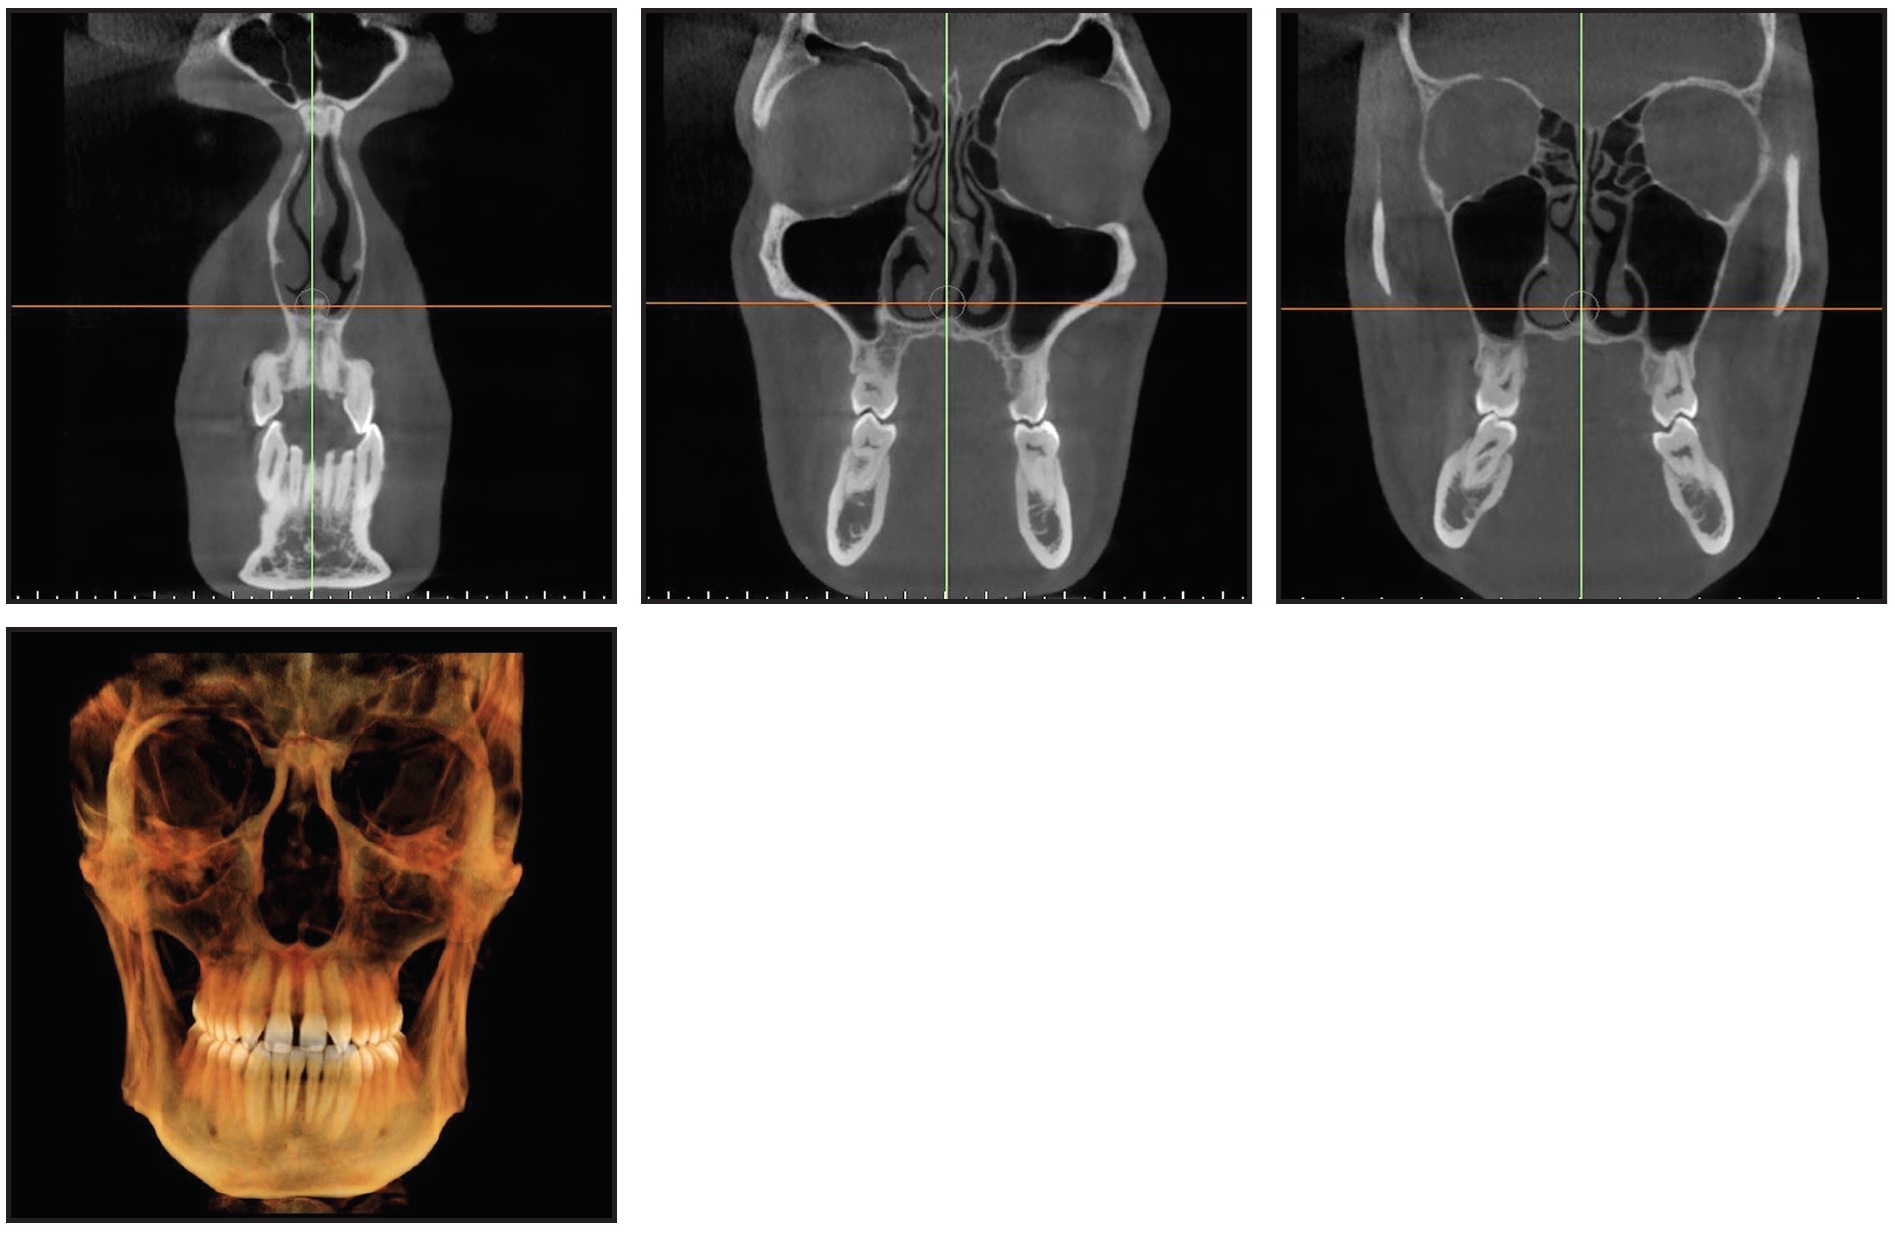

A 25-year-old male presented with a transverse maxillary deficiency, left lateral crossbite, and agenesis of the upper lateral incisors (Fig. 2A). Although he was highly motivated to resolve his malocclusion and obtain a pleasant smile, he refused surgery and demanded esthetic, noninvasive treatment.

Fig. 2 Case 1. 25-year-old male patient with transverse maxillary deficiency and left lateral crossbite before treatment (continued in next image).

From a frontal view, the patient’s face appeared harmonious, with the lower third proportional to the middle and the upper thirds. The mandibular symphysis was deviated to the left. He had a straight profile, a proper nasolabial angle, and a good maxillary bone relationship. Except for the missing upper lateral incisors, all teeth were present, including normally erupted third molars. Bilateral Class I molar relationships were observed, with a Class I canine relationship on the right side and Class II on the left. The lower arch was slightly crowded, and the midline was deviated to the left. The upper arch presented a central diastema and dental asymmetry because of the more distal position of the upper left quadrant. The adjacent teeth had not entirely migrated into the space of the missing lateral incisors, leaving diastemas, especially on the left side. A maxillary transverse deficiency had directly caused the left lateral crossbite (Fig. 2B.

Fig. 2 (cont.) Case 1. 25-year-old male patient with transverse maxillary deficiency and left lateral crossbite before treatment.

Axial cone-beam computed tomography (CBCT) slices at the upper canines and premolars and at the furcation of the first molars confirmed the maxillary transverse deficiency, the left lateral crossbite, and an accentuated curve of Wilson. Cephalometric analysis (Table 1) indicated a Class III relationship (ANB = 0°, Wits appraisal = −5mm). The skeletal growth pattern was normodivergent (FMA = 23.7°). The upper incisors were normally inclined with respect to the palatal plane (U1-PP = 103.6°), and the lower incisors were retroclined relative to the mandibular plane (IMPA = 80.1°).

A two-phase treatment was planned using skeletal maxillary expansion to obtain orthopedic correction of the transverse deficiency, followed by dental alignment. The optimal site for miniscrew insertion was identified on the CBCT scan and superimposed onto the stereolithographic (STL) image of the digital model (Fig. 3). The anteroposterior insertion sites were selected based on the thickness and width of the palatal vault. A 3D surgical guide, properly fitting the morphology of the palate, was then printed using the MAPA System.

Fig. 3 Case 1. Virtual planning of miniscrew insertion sites based on Digital Imaging and Communication in Medicine (DICOM) and stereolithographic (STL) files.